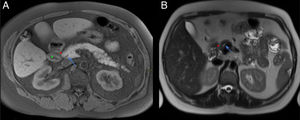

El engrosamiento de la pared del duodeno con estenosis luminal secundaria y quistes en su pared o en el surco son hallazgos infrecuentes en el ACP, cuya presencia haría inclinarse hacia el diagnóstico de PS. Sin embargo, la existencia de una masa hipointensa en T1 con invasión vascular, adenopatías o infiltración del retroperitoneo haría más factible el diagnóstico de ACP (figs. 7 y 8)7,9,10. Otro hallazgo que diferencia el ACP de la PS es una dilatación, tanto del CPP como del colédoco (signo del doble conducto) (figs. 9 y 10)8. El patrón de realce de estas dos entidades en estudios poscontraste es también diferente y ayuda a diferenciar ambas entidades. El ACP presenta escaso realce y de forma homogénea, mientras que la PS suele realzar de forma tardía y heterogénea7.

Varón de 74 años con ictericia y síndrome constitucional. Cortes axiales del abdomen con contraste intravenoso en fase arterial (A) y portal (B). Pequeña masa hipovascular en la cabeza - proceso uncinado del páncreas (flechas rojas, A) que envuelve a la arteria gastroduodenal y condiciona una dilatación de la vía biliar extrahepática e hidrops vesicular (flechas verdes, B).

Mismo caso que la figura anterior. Cortes axiales del abdomen en secuencia T1 con saturación grasa (A) y secuencias HASTE (B). Se observa en el aspecto anterior y medial del páncreas y en contacto con la 2.ª porción duodenal una masa hipointensa (flecha roja, A) identificada previamente en la tomografía computarizada con infiltración del surco pancreaticoduodenal (PD) (asterisco rojo, B). En la secuencia HASTE se observa hidrops vesicular, dilatación del CP (flecha verde en B) y ocupación del surco PD. El diagnóstico final fue de adenocarcinoma de páncreas.

Mujer de 65 años con diarrea crónica. Cortes axiales del abdomen tras administración de CIV en fase portal (A y B). Tenue hipodensidad en la cabeza-proceso uncinado del páncreas que contacta con la vena mesentérica superior (flechas rojas, A). Dilatación de la vía biliar extrahepática y del CP (signo del doble conducto) (flechas verdes, B) y borramiento del surco pancreaticoduodenal (asterisco rojo, A). Hallazgos sugestivos de neoplasia de páncreas.

Mismo paciente de la Figura 9. Cortes axiales del abdomen en secuencia T1 FS poscontraste (VIBE). A y B) Masa hipointensa en cabeza pancreática respecto al resto del páncreas con ocupación del surco pancreaticoduodenal (flecha y asterisco rojos, A) y dilatación de vía biliar extrahepática y del CP (flechas verdes, B). El diagnóstico final fue de adenocarcinoma de páncreas.